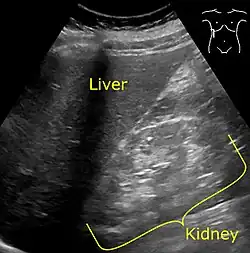

It is recommended that individuals with diabetes have their albumin levels checked annually, beginning immediately after a diagnosis of type 2 diabetes and five years after a diagnosis of type 1 diabetes.[27][30] Medical imaging of the kidneys, generally by ultrasonography, is recommended as part of a differential diagnosis if there is suspicion of urinary tract obstruction, urinary tract infection, kidney stones or polycystic kidney disease.[31] Conformation kidney biopsy should only be performed if non-diabetic kidney disease is suspected.